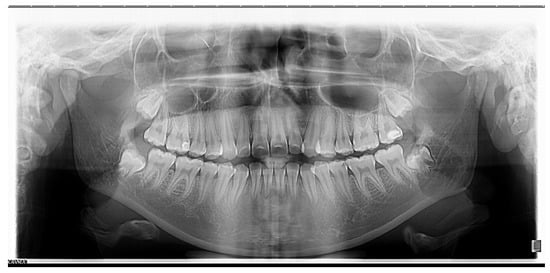

- Skeletal open bite in a 15.7-year-old patient with hyperleptoprosop morphological facial type (N-Gn/Zy-Zy = 111.66), high degree of hyperdivergence (FMA = 39.22°), bimaxillary dento-alveolar protrusion (IF = 120.85°, IMPA = 98.03°), 7 mm skeletal open-bite, and 3 mm vertical inocclusion of the anterior teeth;

- Skeletal class II relationships (SNA = 78.32°, SNB = 73.98°), bilateral half cusp class II molar and canine relationships;

- Bimaxillary anterior crowding.